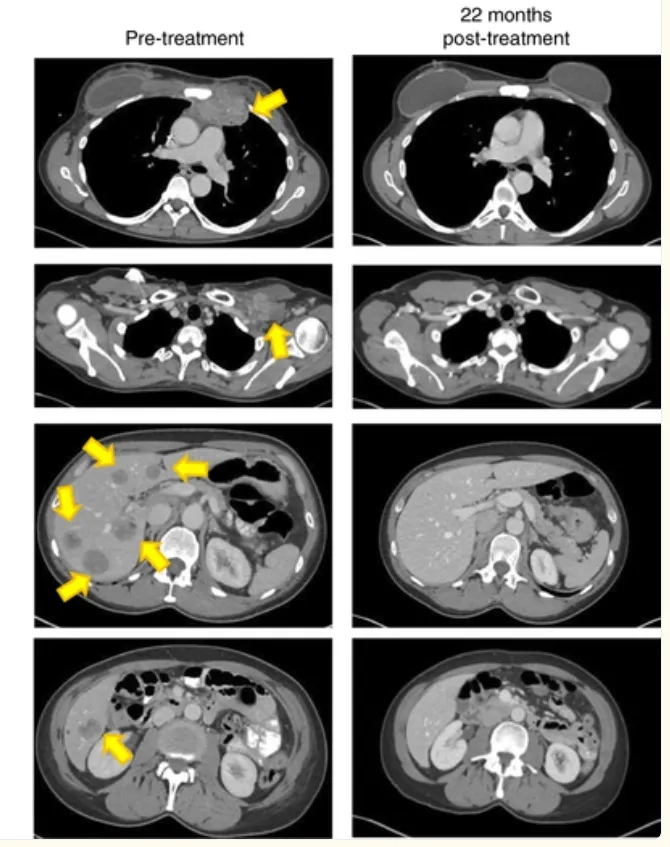

疗效结果远超预期:TIL回输后6周,患者靶肿瘤负荷减少51%;回输22个月时,所有靶病变及非靶病变均实现放射学完全消退(详见下图),截至报道时完全缓解状态已持续超22个月。

▲图源“Nat Med”,版权归原作者所有,如无意中侵犯了知识产权,请联系我们删除